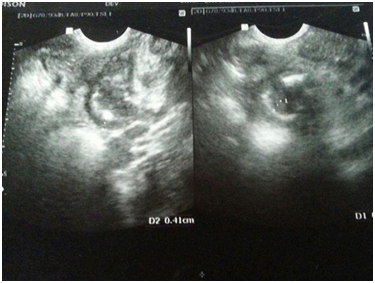

A three year old, male child was brought to the emergency with complaints of pain in abdomen for one day and non passage of stools and flatus for 2 days. There was one episode of bile tinged vomiting on the day of presentation to us. On examination, the child was sick looking, with tachycardia and mild distension of abdomen. The abdomen was guarded and tenderness present in the right para umbilical region along with a vague lump on palpation. An ultrasound was advised which revealed bowel wall thickening with mesenteric lymphadenopathy in the right iliac fossa. The thickened bowel loops showing an angulated intraluminal focus ? foreign body (Figure 1). A Xray abdomen was done which showed an oval foreign body in the mid abdomen overlying spine (Figure 2). The attendents were enquired about possibility of any foreign body ingestion and then they revealed that child had ingested a button cell, 3 days back. In view of these findings and condition of the child, decision to do a laparotomy was taken. Pre-operative routine investigations showed a leukocytosis with WBC counts of 15500 and polymorph count of 89%. Laparotomy was done under general anesthesia. There was a clump of bowel loops present in the right lumber region at the site of palpable lump on clinical examination. After adhesilysis a contained leak of bowel contents along with a perforated meckel’s diverticulum was found. The perforated site was showing a charred circular patch which was stuck up to the adjacent mesentery, which also showed similar charred area (Figure 3). On palpation of meckels diverticulum, a firm circular object was felt, which turned out to be a leaked button cell. This was lodged in the diverticulum, near its apex. The size of button cell was 1 cm x 1 cm. A segmental resection of the meckels was done with end to end anastomosis (Figure 4). The post operative recovery was uneventful. The child was discharged on post op day 7. The child has been in follow up for 2 years now and is doing well. The parents were advised to be carefull with the button cells and keep the child away from them.

Figure 1 An ultrasound showing, bowel wall thickening with mesenteric lymphadenopathy in the right iliac fossa. The thickened bowel loops showing an angulated intraluminal focus? foreign body.